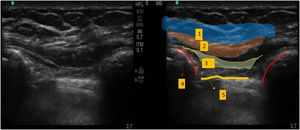

Bloqueo de las ramas del nervio supraclavicularSe situó a la paciente en posición supina, con la cabeza girada hacia la derecha, situándose la sonda por encima de la clavícula (fig. 4-A). Administramos una inyección subcutánea de 10 mL de ropivacaína al 0,25%, con el objetivo de alcanzar las ramas superficiales del nervio supraclavicular (fig. 4-B).

A) Figura esquemática de los nervios del plexo cervical superficial.

1. Nervio occipital menor. 2. Nervio auricular mayor. 3. Nervio cervical transverso. 4. Nervios supraclaviculares. 5. Clavícula. 6. Dermatoma de los nervios supraclaviculares. B) Ecografía del bloqueo de las ramas del nervio supraclavicular.

1. Infiltración subcutánea. 2. Sombra acústica. 3. Clavícula.